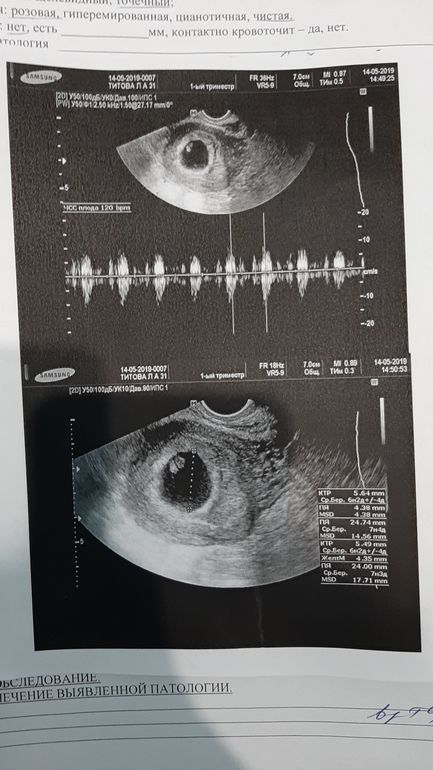

Моя третья беременность после кесареваВсем привет !Спустя 6 лет в нашей семье скоро будет пополнение ,недавно я узнала об этом ,я очень счастлива ,пугает тот факт что это будет третье кесарево ,сейчас лежу в больницы с сильными токсикозом и меня это пугает ,как там мой малыш ,УЗИ еще нескоро ...